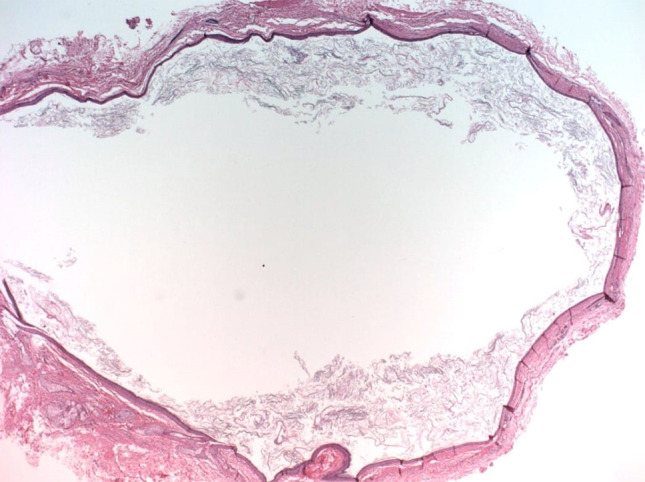

Fig. 4.

Microphotograph showing mature cystic teratoma

A 2 month old female child presented to the ENT OPD with complaints of a progressively increasing left sided neck swelling since birth. The mother also complained of the child having difficulty in feeding for the last 10 days. There was no history of breathing difficulty, noisy breathing or cyanosis. Rest of the history was unremarkable. On examination, there was a globular, cystic, mobile, non-tender mass measuring 5 × 5 cm with well-defined margins observed in the left submandibular region. The overlying skin was normal. (Fig. 1) Intra oral examination showed presence of left buccal mucosa bulge. Contrast enhanced Computed Tomography showed a well-defined lesion showing fat density, a few calcified foci along with heterogeneously enhancing components in the left submandibular region measuring 5 × 4.1 × 3.1, suggestive of teratoma. (Fig. 2) Pre-operative FNAC was suggestive of a lipomatous lesion. The patient was planned for excision of the mass under general anaesthesia. Intraoperative findings included a well capsulated mass extending up to the floor of the mouth. All the vital neurovascular structures were preserved and the mass was removed in toto along with the ipsilateral submandibular gland. Grossly it was 4 × 4.5 × 3 cm size encapsulated solid mass with a pale yellow bosselated surface possibly extending into the submandibular gland. (Fig. 3) Microscopic examination of the specimen showed features of mature cystic teratoma. (Fig. 4).